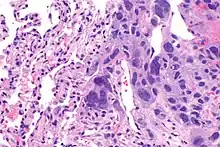

Choriocarcinomas are exceptionally rare which account for 2.1%-3.4% of all OGCTs.[14] Under gross examination, the syncytiotrophoblast cells are aligned in a plexiform arrangement with the mononucleated cytotrophoblast cells surrounding the foci of the hemorrhage.[1] Choriocarcinomas can be divided into gestational choriocarcinomas and non-gestational choriocarcinomas which have immunohistochemical differences.[15]